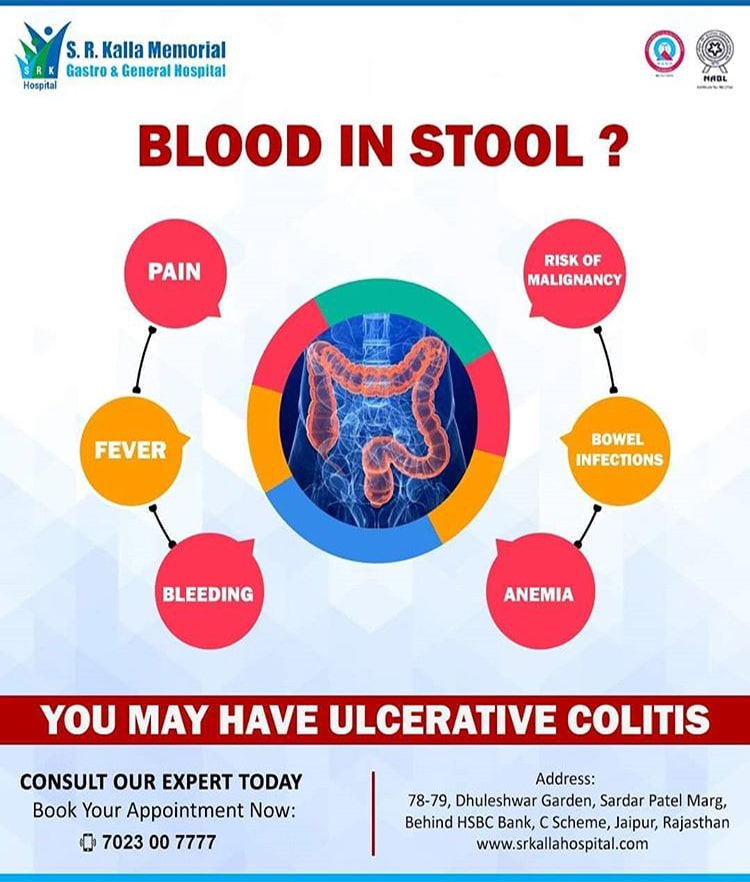

I was a patient of Ulcerative Colitis for the past 4 years and was under treatment at SR Kalla Hospital. I must thank doctors here for my diagnosis and good treatment.